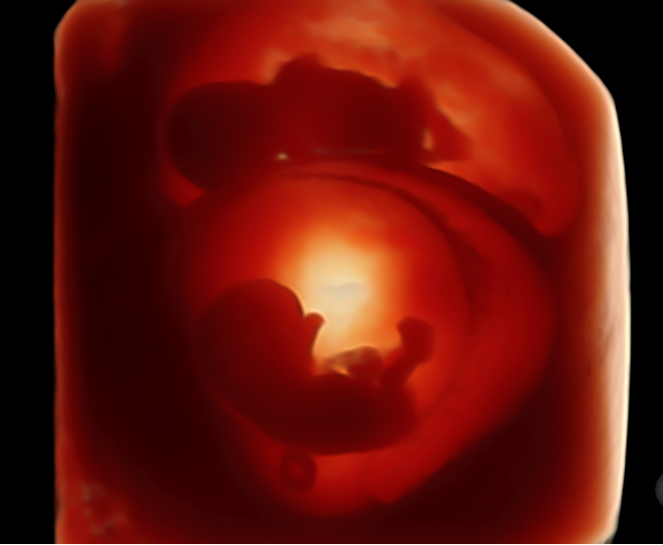

为满足大家需求,近期,金普妇幼保健院新引进了一台GE-Voluson 金标E10彩色多普勒超声诊断仪,它搭载煊光、煊影、煊流成像技术,能够360°高清立体、超真动态地显示宝宝的实时活动图像;动态呈现胎儿在宫内的发育及活动情况;成熟应用于胎儿早中孕期筛查、容积成像等方面。将为临床提供更超清、更精准、更直观的图像数据,是目前超声诊断系统中功能最强大、最高端的彩超诊断仪之一,堪称:“胎儿排畸新王者”。标志着我院产前及妇科超声诊断技术迈上新的台阶。

3、画质惊艳堪比IMAX电影效果,全面颠覆传统视觉理念

煊影成像技术提供更多更精准的图像数据,实现胎儿影像360°超真动态演示,成像立体感强,画质堪比IMAX电影效果,全面颠覆传统视觉理念。